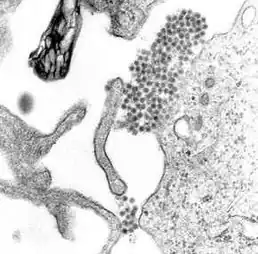

![]() Infekce virem horečky Dengue; patrné jsou viriony | |

Čeleď Flaviviridae zahrnuje 4 rody: Flavivirus, Pegivirus, Pestivirus a Hepacivirus, skupinu virů hepatitidy C. Flaviviry jsou v porovnání s togaviry menší, dosahují průměrné velikosti 40-60 nm. Genom tvoří jedna molekula jednovláknové RNA s pozitivní polaritou (+). Viriony obsahují 3 strukturální proteiny – obalový glykoprotein, dřeňový protein a membránový protein. Replikují se v cytoplazmě a lipidový obal získávají pučením do cytoplazmatických vezikulů. Podobně jako togaviry vykazují hemaglutinační aktivitu v závislosti na pH.[1]